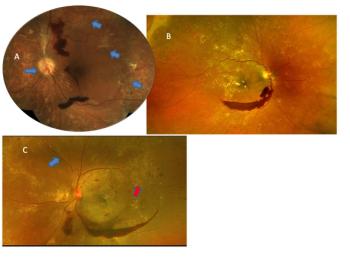

Vision loss caused by diabetic retinopathy comes in different packages.

ODs must pay close attention and manage all factors responsible for disease progression to improve the patient’s final outcome. The patient in this case report shows the importance of such management.

Trace the path of diabetic retinopathy disease via images.